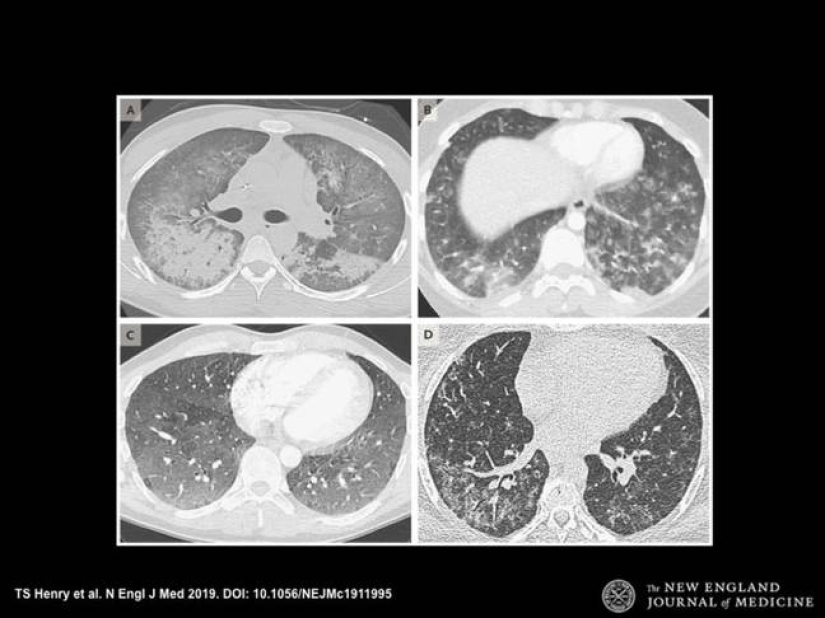

Doctors decided to publish X-rays of smokers' lungs after a series of deaths associated with the use of vaping to warn everyone about its harm.

A fashionable hobby brings young people to the grave, who are happy to inhale fragrant smoke. Harmless, at first glance, infatuation leads to irreversible consequences. X-rays of the lungs of vape smokers are irrefutable proof of the harm of electronic hookahs. We hope this information will pop up in your head before the next puff.